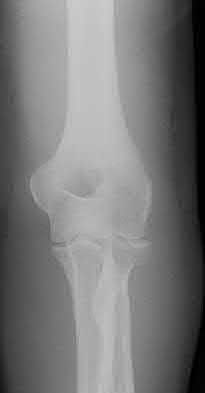

1. # A 32-year-old male sustains the injury shown in Figure A and undergoes treatment as shown in Figure B. Following placement of this implant, what is the best technique to confirm it is not too proud proximally?

1. Lateral radiograph of the knee

2. AP radiograph of the knee

3. Oblique radiographs of the knee

4. Merchant radiograph of the knee

5. Internally rotated 45 degree view of the knee Corrent answer: 1

The safe zone for tibial nail placement as seen on radiographs is just medial to the lateral tibial spine on the anteroposterior radiograph and immediately adjacent and anterior to the articular surface as visualized on the lateral radiograph.

Tornetta et al specifically located the safe zone for nail entry in a study using fresh frozen cadaver knees. The authors found that the safe zone for nail placement is located 9.1+/-5 millimeters lateral to the midline of the plateau and three millimeters lateral to the center of the tibial tubercle. The width of the safe zone averaged 22.9 millimeters and was as narrow as 12.6 millimeters.

The starting point of the of the nail can be best viewed on the lateral knee radiograph, an example of which is shown in Illustration A. Illustration B shows the "sweet spot" for nail insertion as defined by Tornetta.